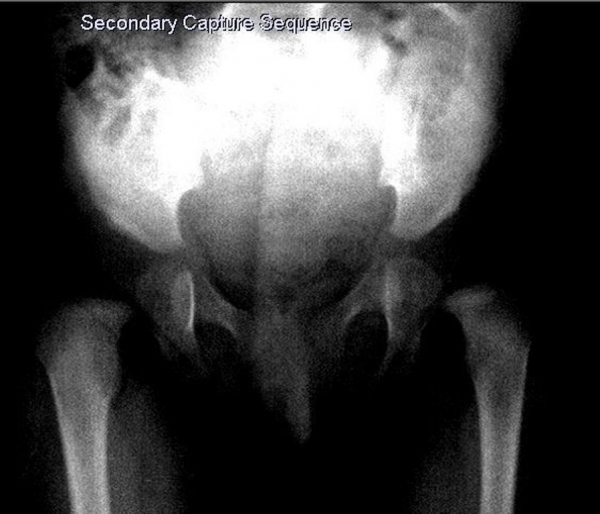

А на рентгене -- полный врожденный вывих, головка лежит вне сустава.

Тактика лечения -- другая, прогнозы - другие.

Таким образом видим полное соответствие УЗИ картины -- рентгенограмме.